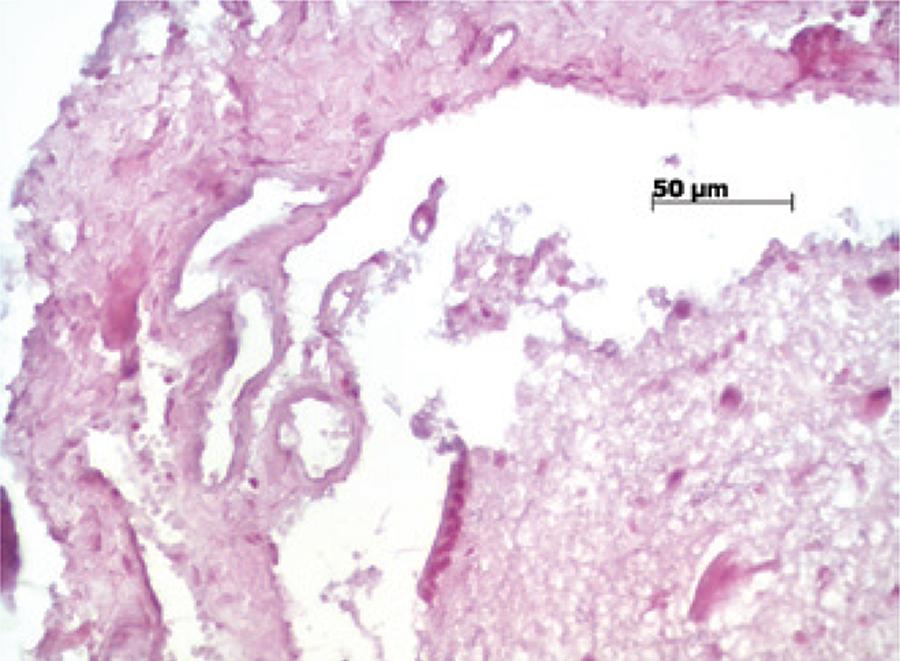

: Trinta ratos Wistar foram randomizados em cinco grupos: o primeiro foi um grupo controle, submetido somente à durotomia. Os outros também foram submetidos à durotomia, porém sofreram sutura simples, reparo com membrana de colágeno bovino, tela de silicone e tela de silicone com sutura. Os animais foram sacrificados, e a coluna foi submetida à avaliação histológica com um escore (variando de zero a 3) para inflamação, neovascularização e fibrose.

Resultados

: A fibrose foi significativamente diferente, comparando-se sutura simples e tela de silicone (p=0,005) e sutura simples e tela com fio de sutura (p=0,015), demonstrando que a fibrose foi mais intensa quando um corpo estranho foi utilizado na reparação. Membrana bovina foi significativamente diferente da tela mais sutura (p=0,011) em relação à vascularização. A inflamação foi significativamente diferente entre os grupos submetidos à sutura simples e ao reparo com membrana de colágeno bovino.